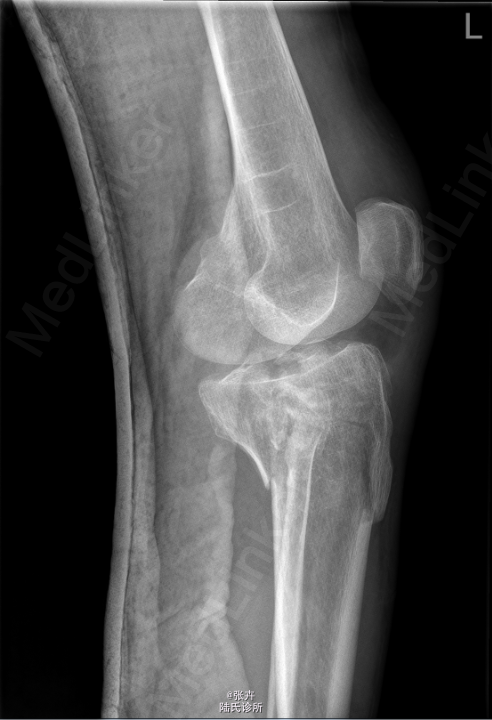

患者,男,50岁,因“外伤致左膝肿痛伴活动受限1天”入院。 患者1天前在工地干活时摔伤,左膝着地,当即感左膝疼痛,呈持续剧痛,左膝关节活动受限,左下肢不能站立及行走,无左下肢麻木。我院CT提示:左侧胫骨平台及左侧腓骨头粉碎性骨折,左膝关节积液、积脂血症。建议手术治疗,遂拟“左胫骨平台骨折”收住入院。

查体:左小腿上段肿胀明显,皮温不高,局部皮肤张力性水泡,无出血、渗出等,左膝关节活动受限,关节间隙,压痛明显。 我院CT提示:左侧胫骨平台及左侧腓骨头粉碎性骨折,左膝关节积液、积脂血症

初步诊断:左胫骨平台骨折。行左胫骨平台骨折切复内固定+人工骨植骨术。